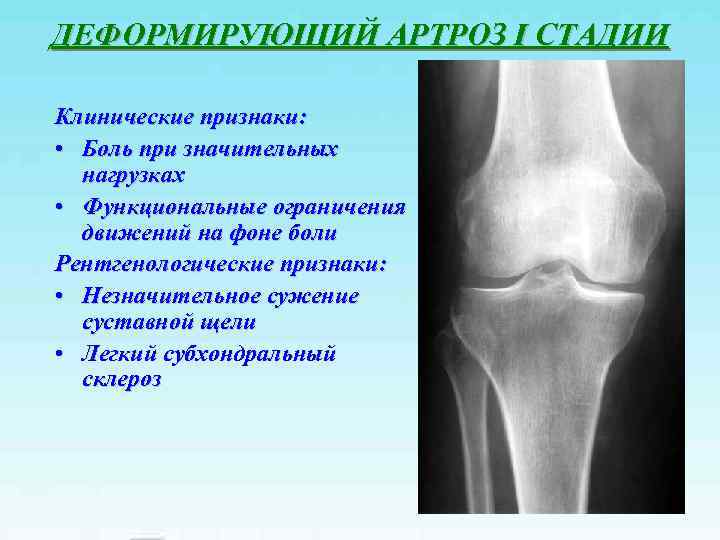

Медицинские снимки: рентген коленного сустава при остеопорозе